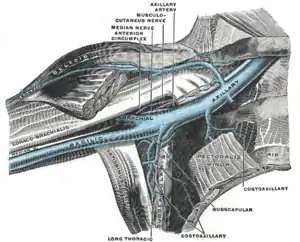

| Anterior view of right upper limb and thorax | |